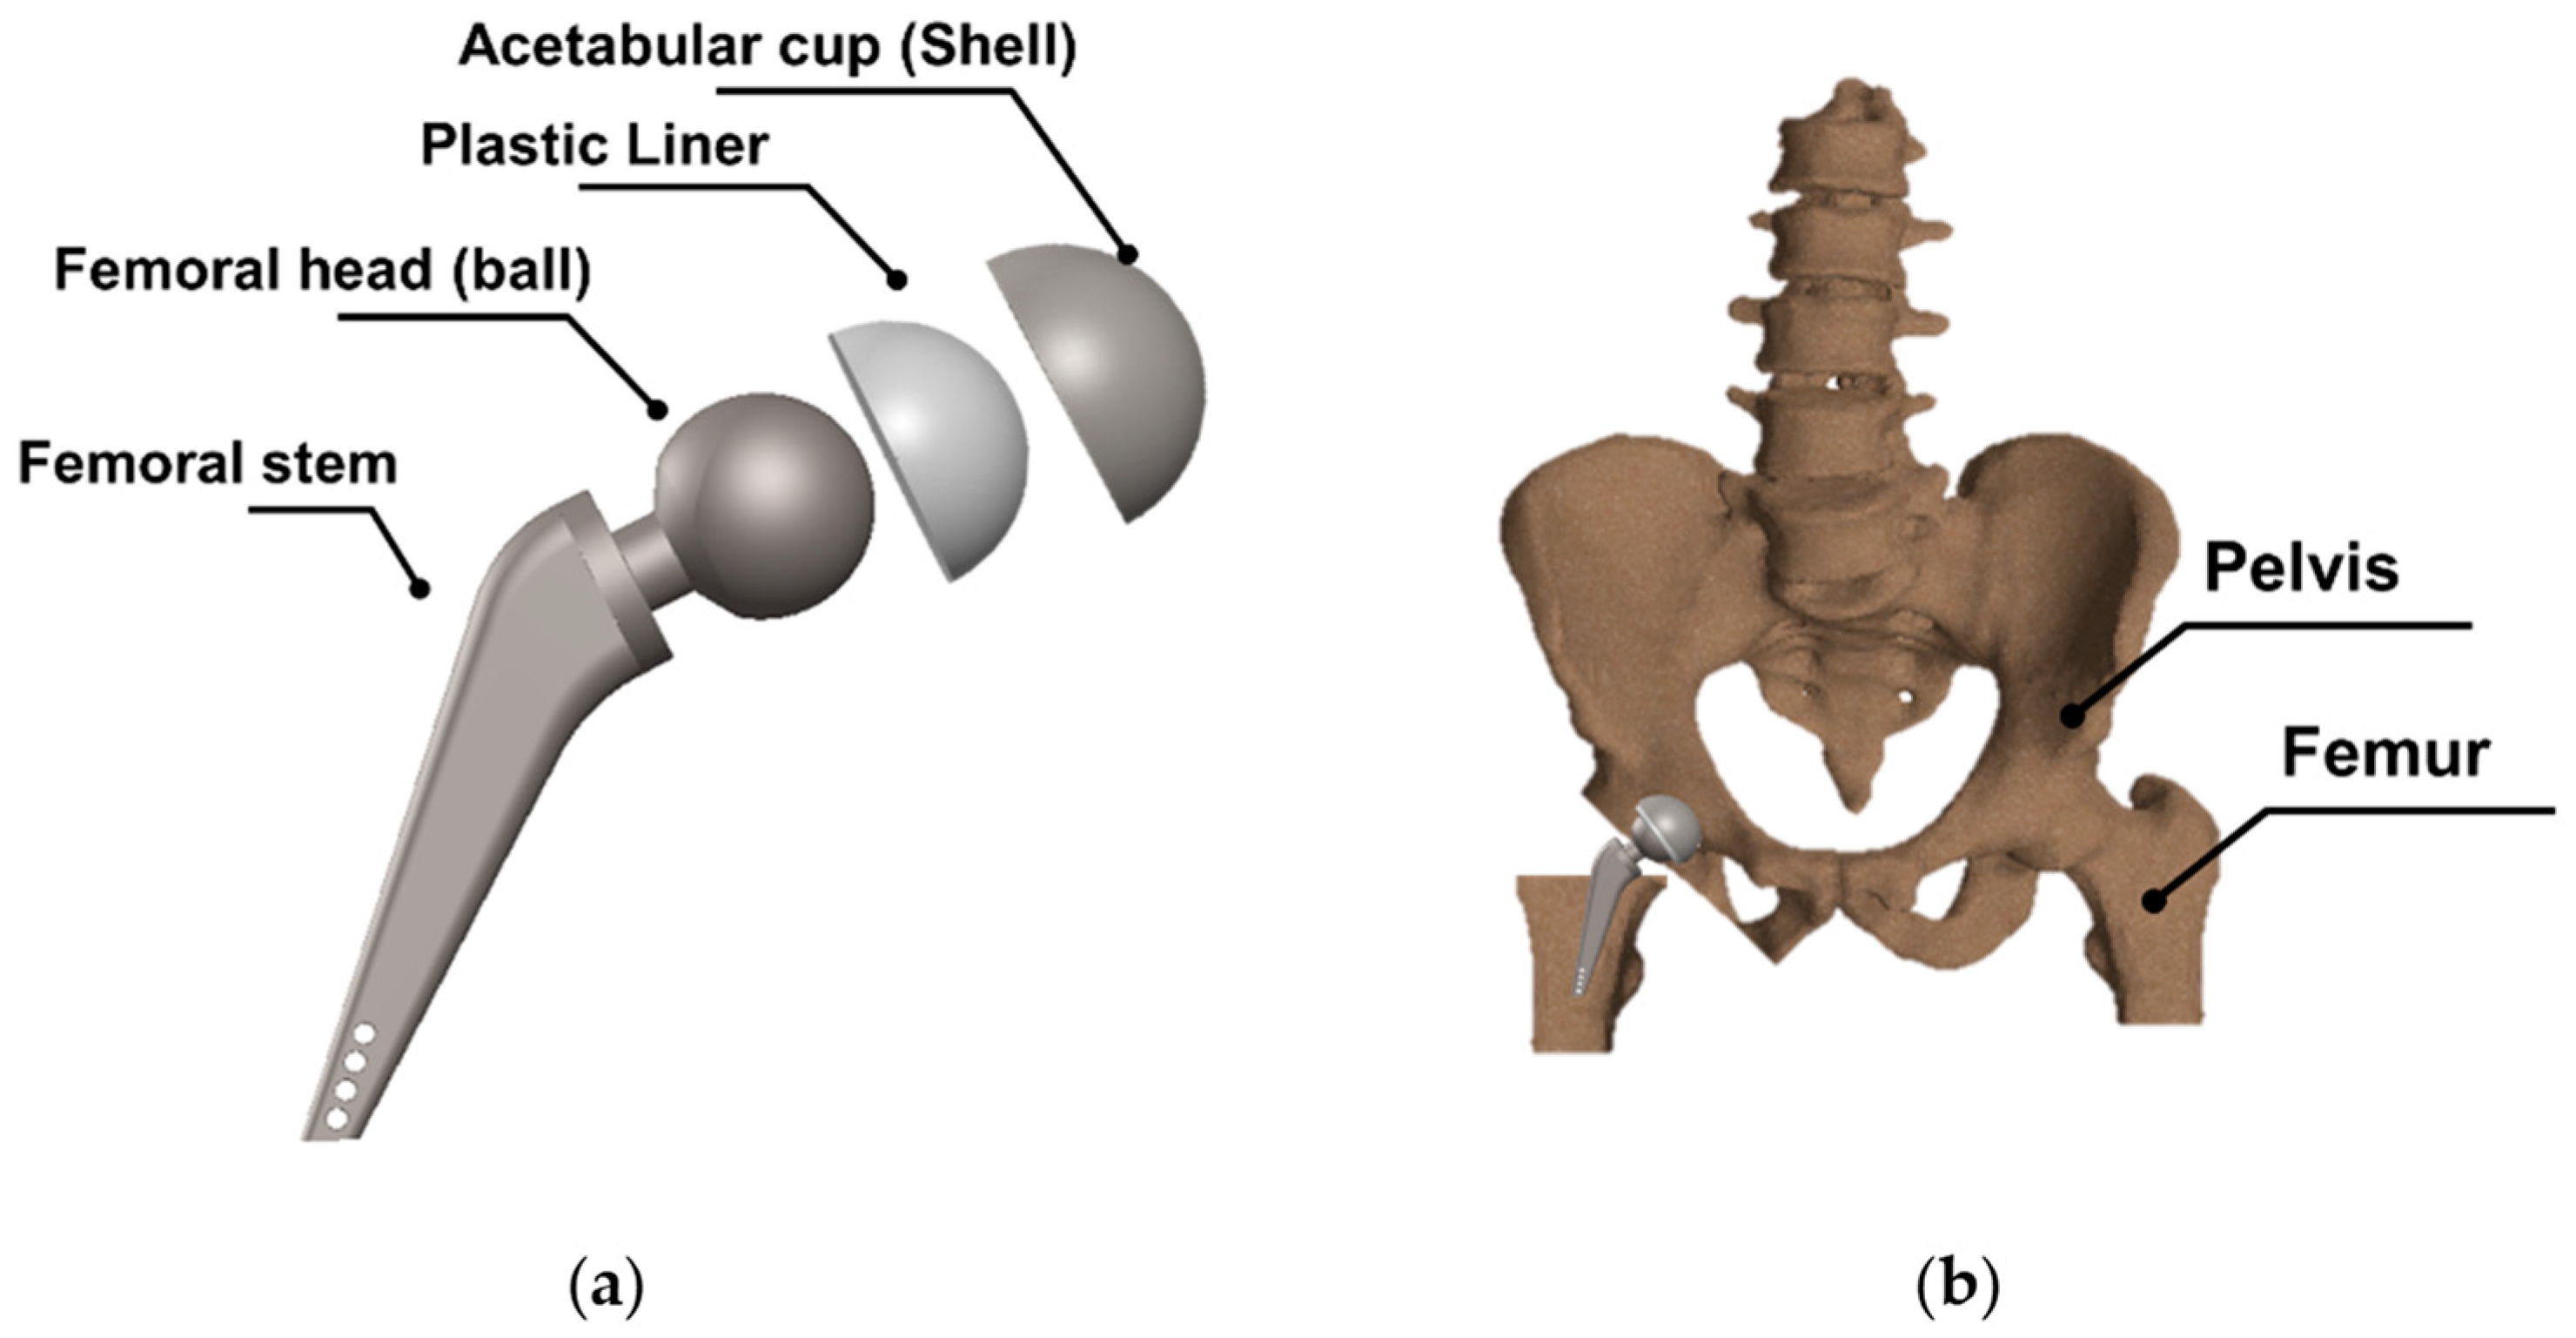

:1. Introduction

2.3. Medical Application